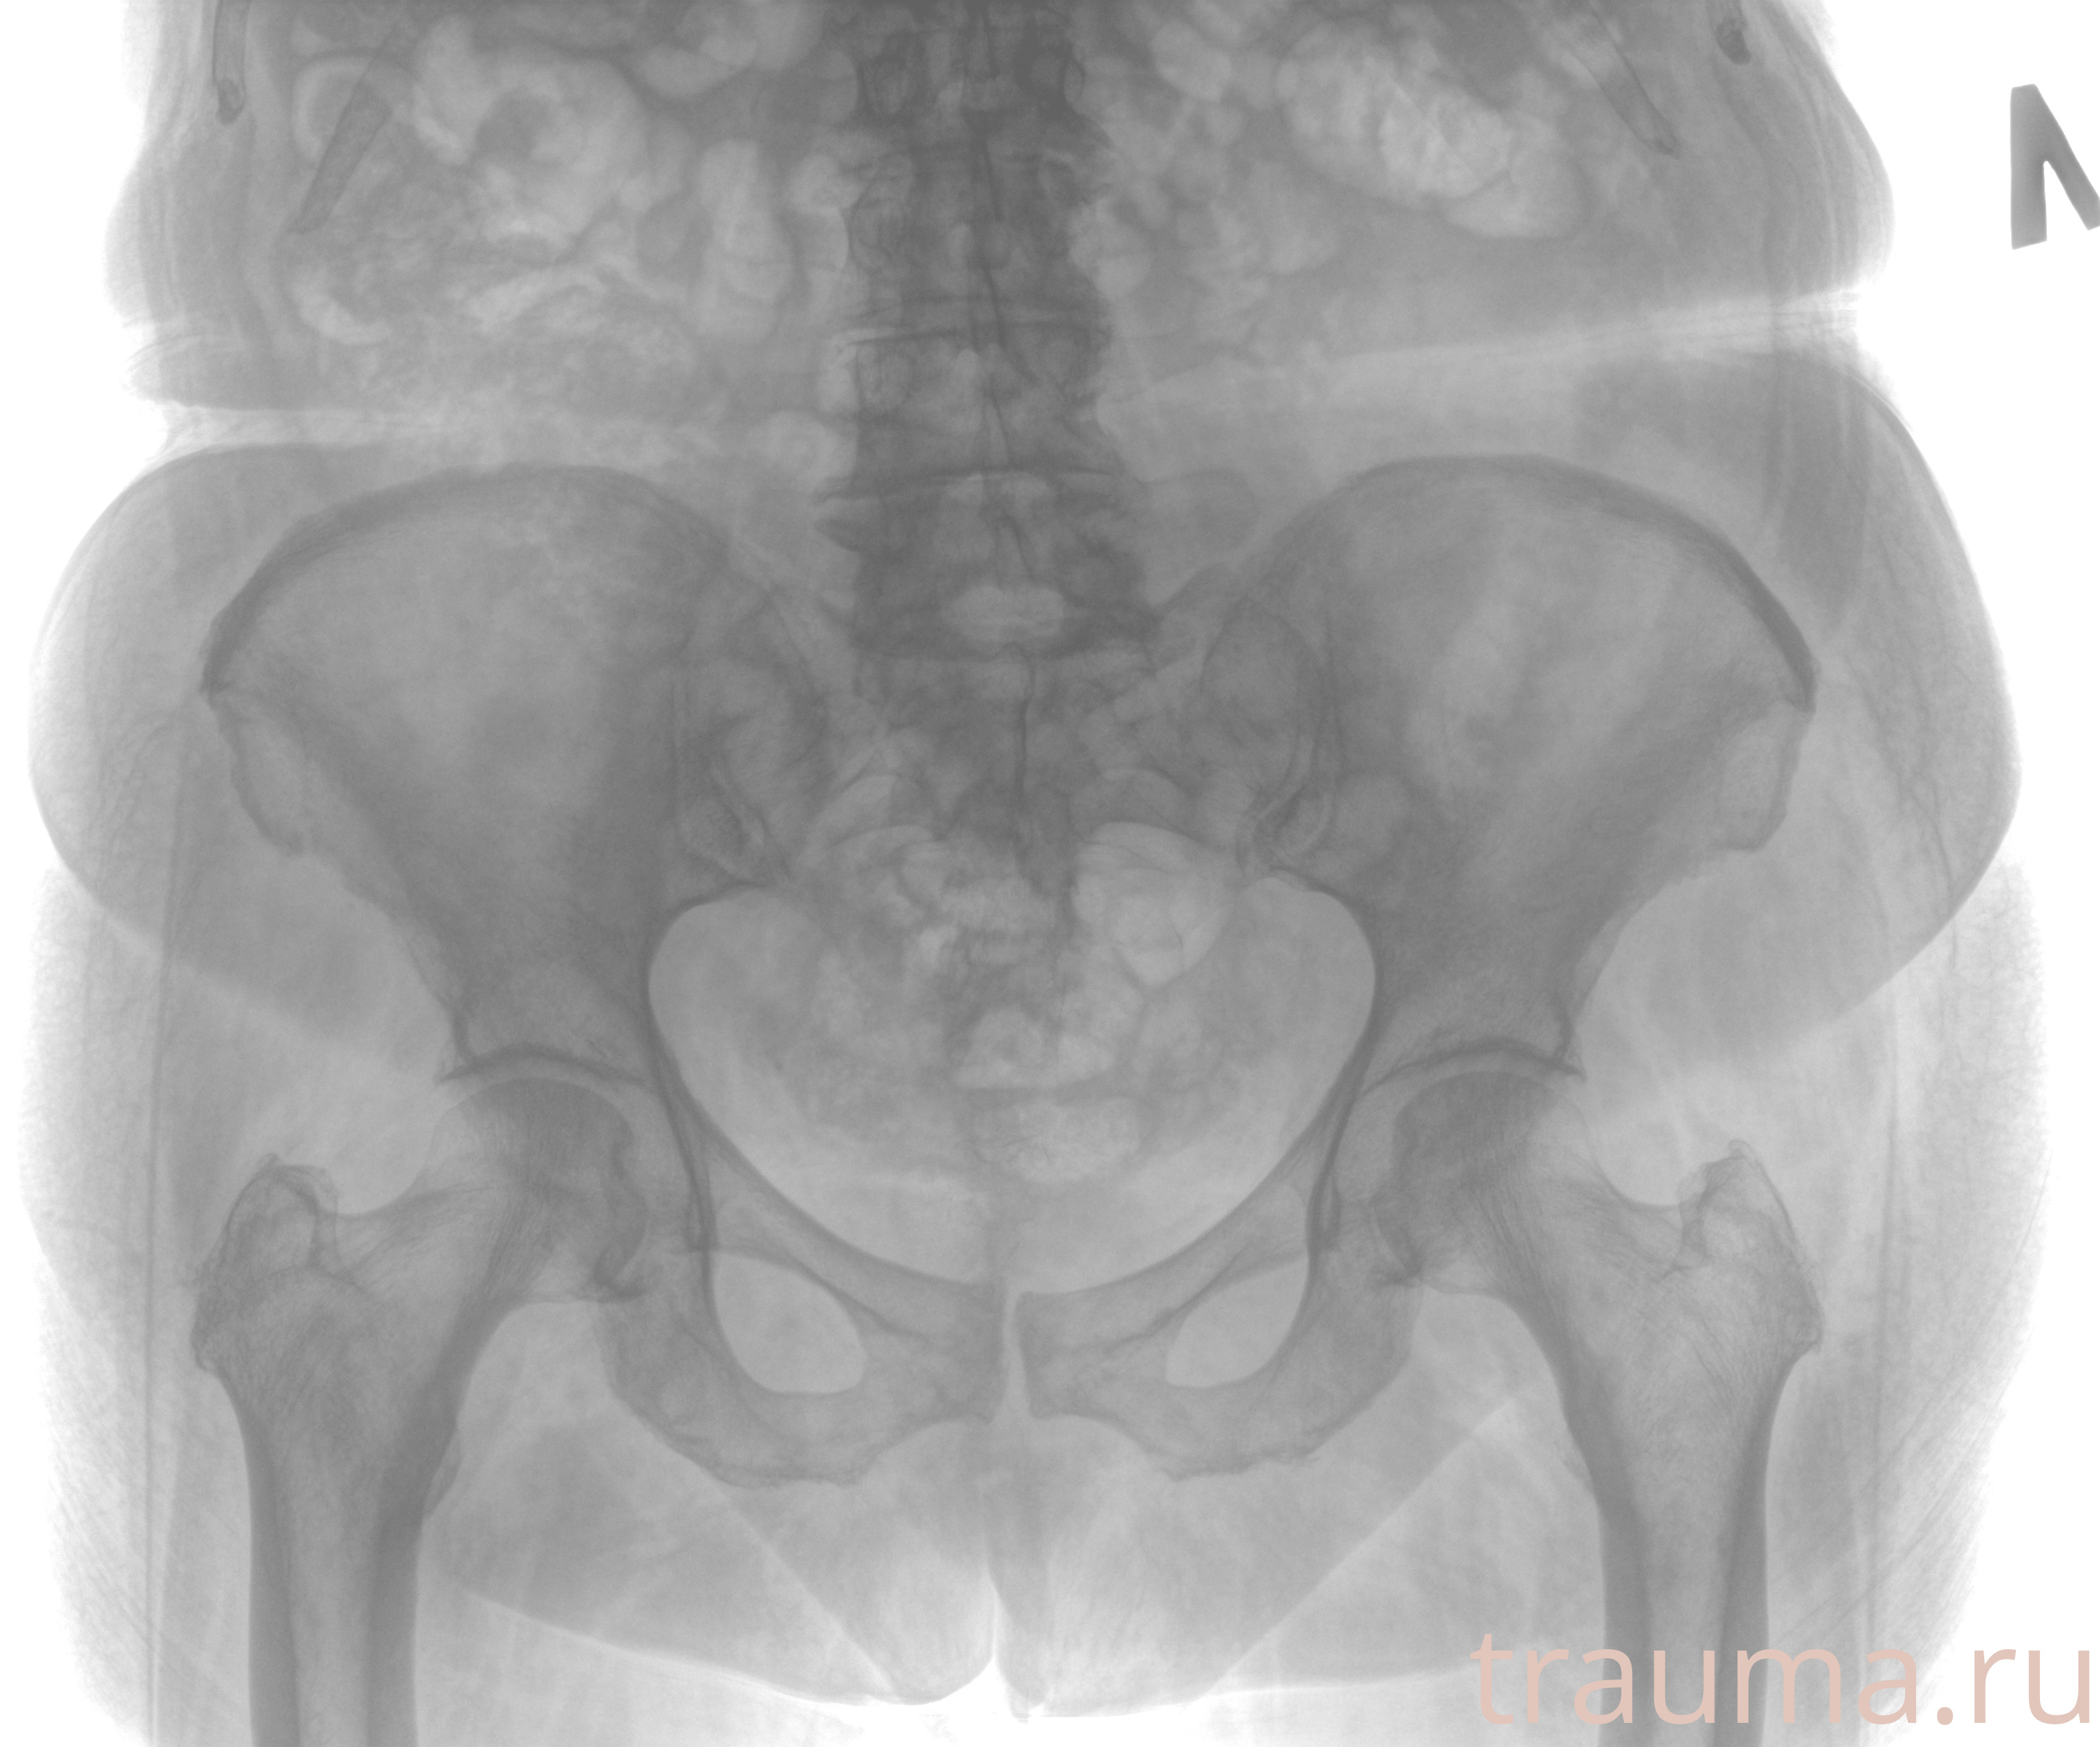

Рентген на дому: по вашему адресу приезжает врач-рентгенолог, травматолог-ортопед с мобильным рентгеновским аппаратом, проводит диагностику травмы или заболевания, делает необходимые рентгенограммы, дает рекомендации по дальнейшему лечению. Получить качественные снимки в домашних условиях возможно благодаря уникальной методике, разработанной МосРентген Центром для института  Склифосовского